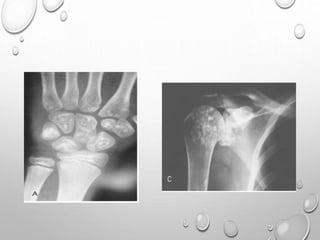

HANDS – LONG TUBULAR BONES ARE SHORT THICK , DELAY APPEARANCE OF IRREGULAR

EPYPHYSES

MARKEDLY SHORTENED ULNA , RADIUS AT WRIST , ESPECIALLY AT CENTER THEY ARE

HYOPLASTIC….GIVING V APPEARANCE

CARPALS , TARSALS AND LONG TUBULAR BONES OF HAND ,SOMETIMES

FEET ARE SHORT AND THICK

HAND :

PROXIMAL ENDS OF METACARPALS TAPER AND IN OLDER

CHILDREN

DISTAL END OF RADIUS , ULNA SLOPE TOWARD EACH

OTHER. METACARPALS , PHALANGES ARE SHORT AND WIDE